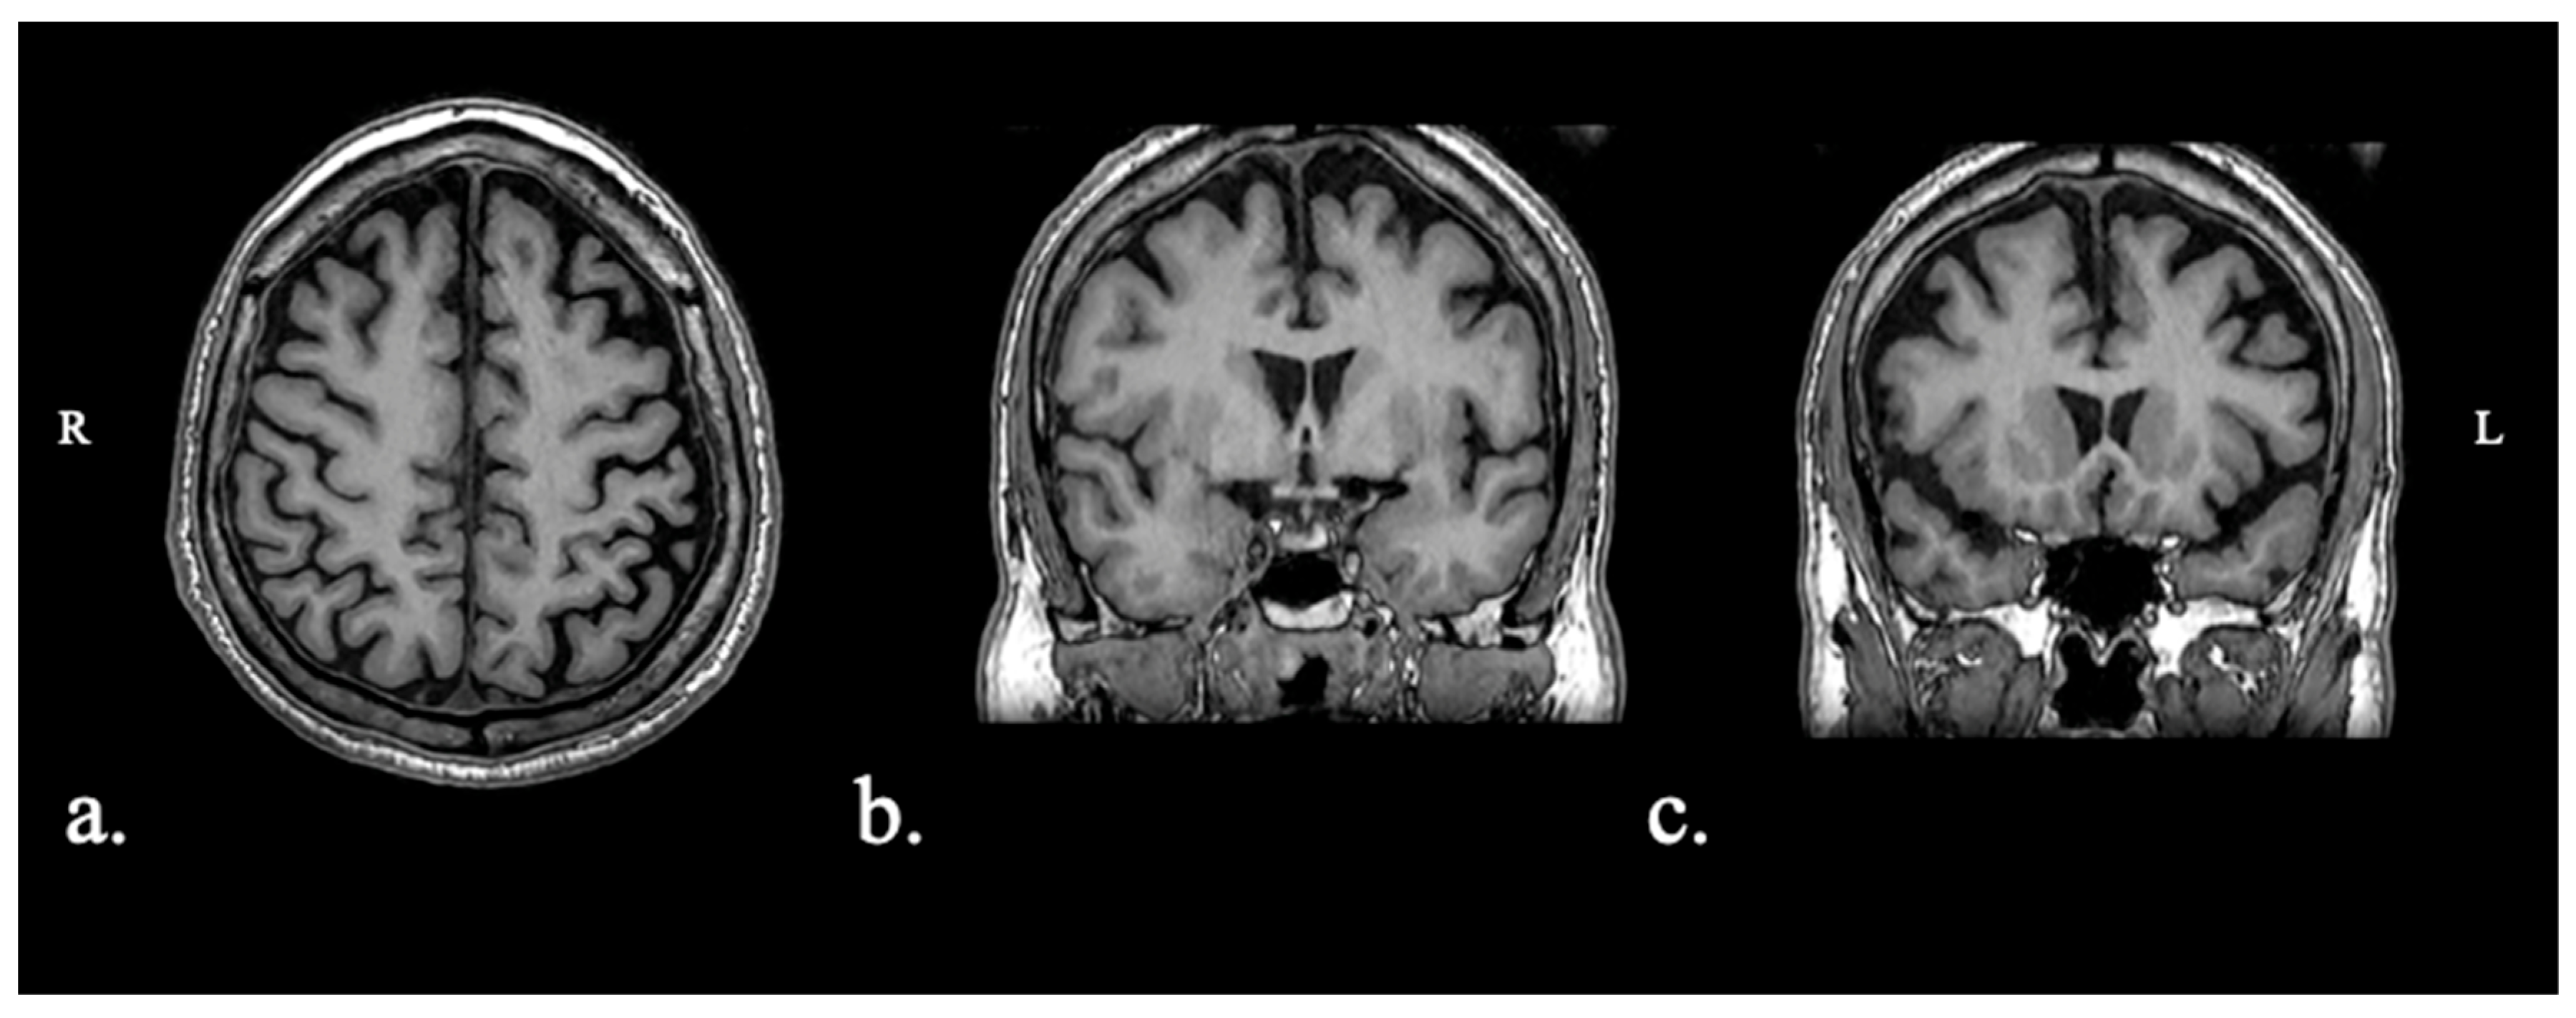

2.1.1. Patient FAY

2.1.2. Patient XTY

2.1.3. Patient ADY

2.1.4. Patient IZS